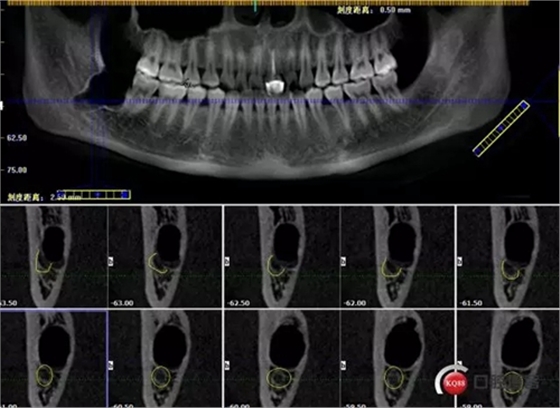

1498615726_560454.png

牙齒中1/3神經(jīng)管偏頰側(cè)